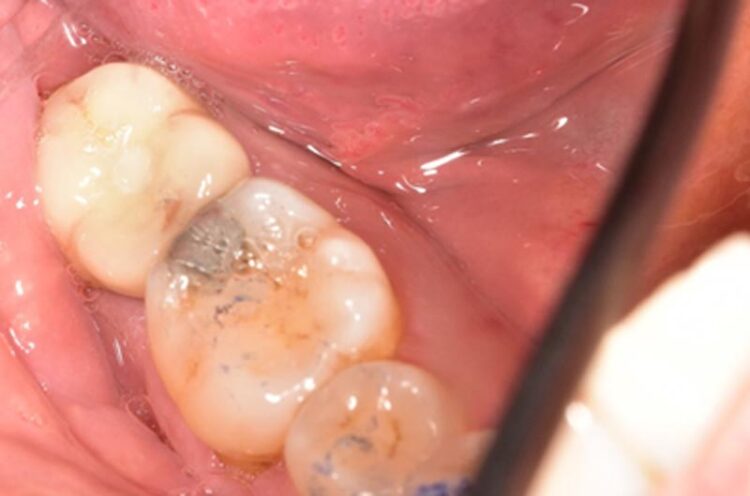

After three months the healing abutment was then removed. The presence of the healing abutment facilitated the development of an emergence profile from the implant platform during the healing phase. A fixture level impression was taken and a screw-retained crown with the screw emerging in the mid-occlusal area was fabricated. The crown was made on a zirconia framework on a hybrid base abutment layered with e.max ceramic with ultra-polished zirconia subgingivally.

The occlusal profile was carefully contoured to avoid overloading of the implant, but of course to still provide functional benefit.

This case beautifully demonstrates the emergence profile that the tissue level implants facilitate along with the ease of cleansability for the patient, even when the prosthesis is placed posteriorly in difficult to reach areas.